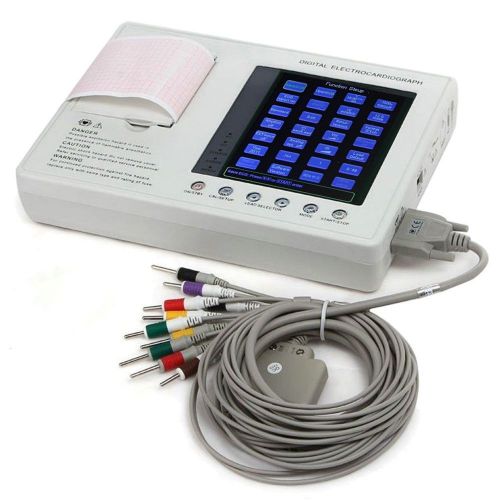

7-Inch Color LCD Digital 3-channel 12-lead Electrocardiograph EKG ECG Machine OO

7-Inch Color LCD Digital 3-channel 12-lead Electrocardiograph EKG ECG Machine UU

7-Inch Color LCD Digital 3-channel 12-lead Electrocardiograph EKG ECG Machine CA

Portable Digital 1-channel Electrocardiograph ECG/EKG Machine*CE *FDA TOP A